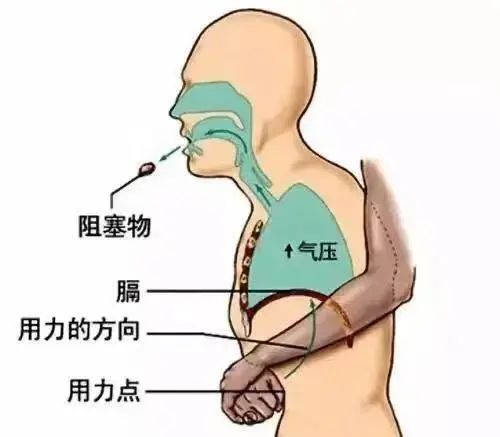

若呛入异物后迅速出现不能咳嗽或无效咳嗽、不能说话、呼吸困难、口唇青紫等表现,说明异物完全堵塞气道,可行海姆立克急救法进行急救。具体操作如下:

对于1岁以上及成人,施救者站于患者背后,双手环抱其腰部,一手握拳,拇指顶住患者上腹部(肚脐和肋骨之间的部分),另一只手张开握在拳头上,快速向内、向上方冲击,一次不成功可多试几次。